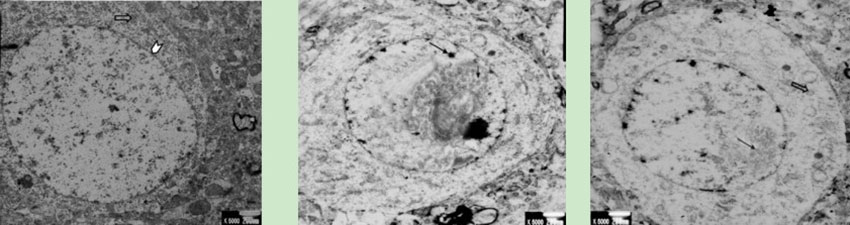

透射電鏡

透射電鏡 800/